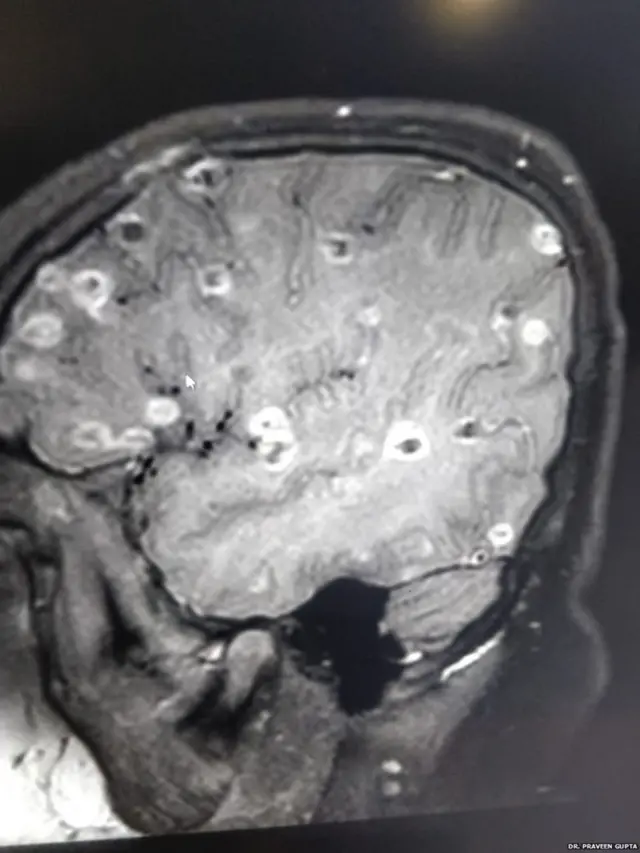

આઠ વર્ષની બાળકીના મગજમાં કૃમિનાં 100થી વધું ઈંડાં જોવાં મળ્યાં. દીકરી માથામાં દુખાવાની ફરિયાદ રોજ શા માટે કરતી હતી, તેને વારંવાર વાઈ કેમ આવતી હતી એ તેના માતા-પિતા સમજી શકતાં ન હતાં.

"બાળકીના મગજમાં 100થી વધુ ટેપવર્મ એટલે કે કૃમિના ઈંડાં હતાં, જે નાનાં-નાનાં ક્લૉટના સ્વરૂપમાં જોવાં મળ્યાં હતાં."

એ બાળકીને ડૉ. પ્રવીણ ગુપ્તા પાસે લાવવામાં આવી ત્યારે તેનું સિટી સ્કેન કરવામાં આવ્યું હતું. તેમાં જાણવા મળ્યું હતું કે બાળકી ન્યૂરોસિસ્ટિસેરસોસિસથી પીડાઈ રહી છે.

ડૉ. પ્રવીણ ગુપ્તાએ કહ્યું હતું, "બાળકીને હોસ્પિટલે લાવવામાં આવી ત્યારે એ બેભાન હાલતમાં હતી. સિટી સ્કેનમાં તેના દિમાગમાં સફેદ ડાધ જોવા મળ્યાં હતાં.”

"એ ડાઘ બીજું કંઈ નહીં, કૃમિનાં ઈંડા હતાં અને પણ એક-બે નહીં, 100થી વધું હતાં."

બાળકીને ડૉ. પ્રવીણ ગુપ્તા પાસે લાવવામાં આવી ત્યારે તેના દિમાગ પરનું પ્રેશર ઘણું વધી ચૂક્યું હતું. ઈંડાંનું દિમાગ પર એટલું દબાણ હતું કે બાળકીનું મગજ કામ કરતું બંધ થઈ ગયું હતું.

ડૉ. ગુપ્તાના જણાવ્યા મુજબ, બાળકીના દિમાગમાં ઈંડાંની સંખ્યા સતત વધી રહી હતી. એ ઈંડા સોજા અને વાઈનું કારણ બનતાં હતાં.